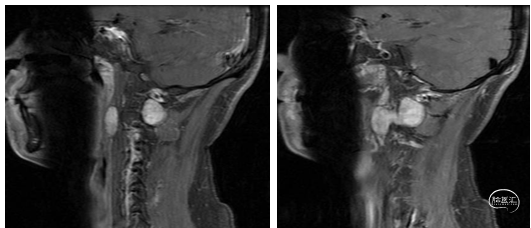

术前颈椎3D-CT如下:

图1 颈椎CT检查提示:C1-C2水平椎管内髓外-右侧椎间孔-右侧咽旁间隙不规则肿物,密度不均匀,难准确测量,范围约49mm×29mm,推移邻近水平脊髓,增强扫描病灶不均匀轻度强化等。颈部CTA示:肿物向外推移邻近右侧颈内动脉,向内挤压右侧椎动脉等。